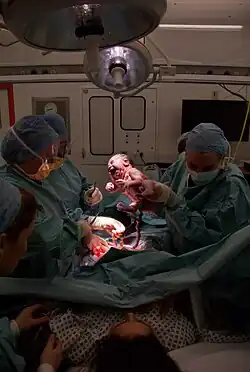

Selected image –

General images –